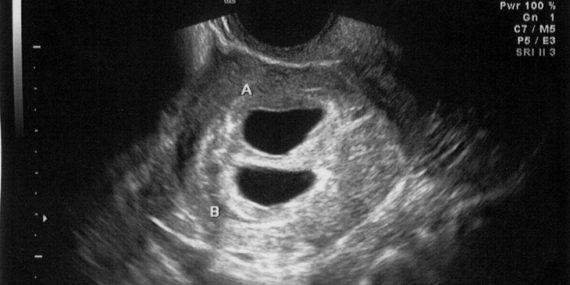

Η Τζέσικα Άλεν δήλωσε στο Inside Edition πως αρχικά πίστεψε ότι περιμένει δίδυμα μετά από ένα υπέρηχο, ο οποίος έδειξε ότι υπήρχαν δύο χτύποι καρδιάς. Αλλά μόνο μετά τη γέννηση, που έλαβε χώρα με καισαρική τομή, έγινε σαφές ότι είχε συμβεί κάτι ασυνήθιστο.

“Ήταν σε ξεχωριστά σάκους”, δήλωσε ο Τζάσπερ στο Inside Edition . Αποδείχθηκε επίσης ότι το παιδί της Τζέσικα και του Τζάσπερ, ένα μικρό αγόρι που ονόμασαν Malachi, ήταν περίπου τρεις εβδομάδες νεότερο από το άλλο μωρό. Δημιουργήθηκε σχεδόν ένα μήνα μετά την εμφύτευση του άλλου μωρού λόγω του ασυνήθιστου γεγονότος ότι η Τζέσικα συνέχιζε να έχει ωορρηξία.